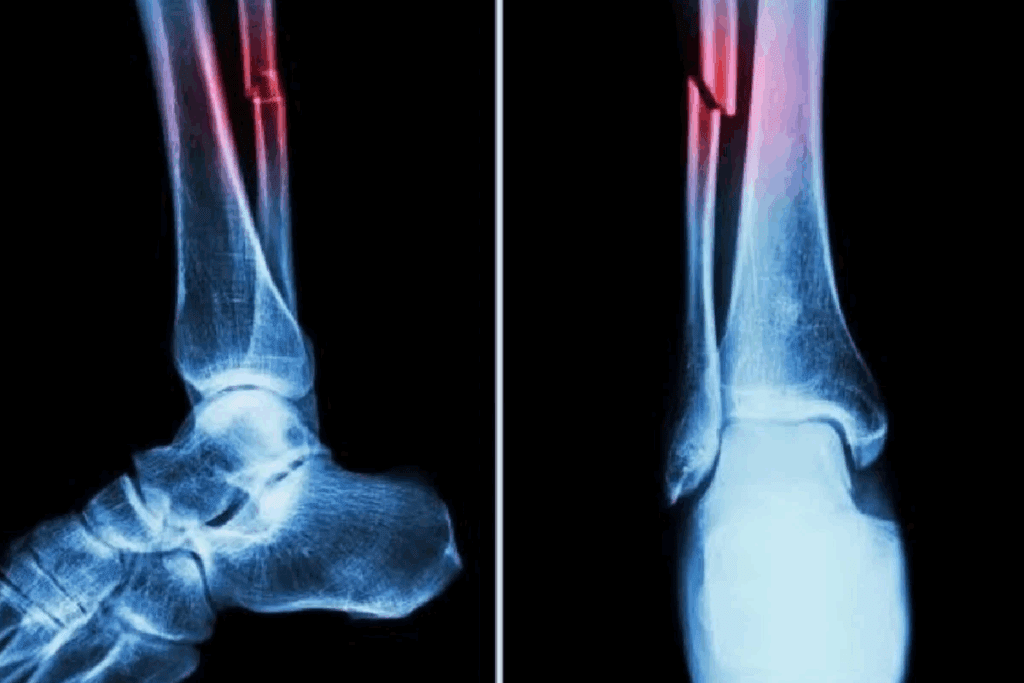

Lower Extremity and Joint Fractures

Ankle Joint Fracture Rehabilitation

Ankle joint fractures need careful rehab to get back to normal and avoid future issues. The rehab process includes rest, physical therapy, and slowly getting back to activities that put weight on the ankle. It’s key to regain strength and move freely again.

“The rehab plan for ankle fractures should match the patient’s needs and the fracture’s severity,” say orthopedic experts.